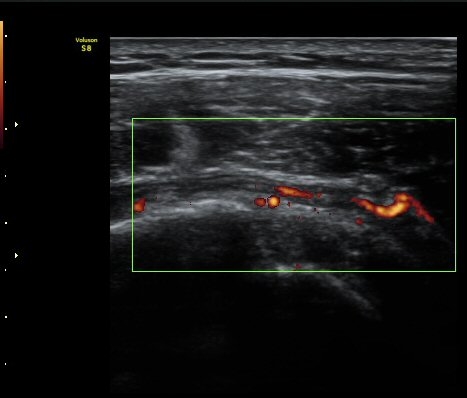

±Ø»ó°Ç Á¾´Ü¸é°Ë»ç¿¡¼­ Á¤¸Æ³¶³» ¼ö¾×Àú·ù¿Í ±Ø»ó°Ç³» ¼®È¸È­À½¿µÀÌ °üÂûµÈ´Ù(±×¸² 2, 3).

ÆÄ¿öµµÇ÷¯°Ë»ç¿¡¼­ ±Ø»ó°Ç°ú Á¡¾×³¶ÁÖÀ§¿¡¼­ ¼ö¾×Àú·ù°¡ °üÂûµÈ´Ù(±×¸² 6, 7).